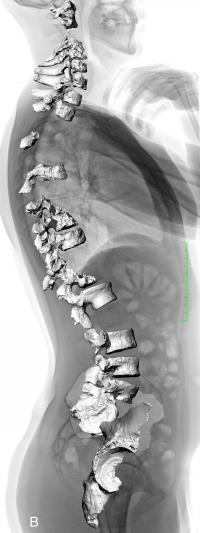

科研人员报告了对一个尼安德特人个体的脊柱和骨盆的重新分析,它表明了脊柱弯曲度类似于现代人。对尼安的特人的姿态的重建各不相同,早期的重建把尼安德特人描述为弓背不完全直立,而近来的研究提示,尼安德特人的脊柱弯曲度比现代人更平。Martin Haeusler、Erik Trinkaus及其同事重新评估了La Chapelle-aux-Saints的尼安德特人个体的脊柱残骸,使用一个骨盆重建推断了这个个体的脊柱弯曲度角度。考虑到这个个体的可能的骨关节炎和其他衰老相关退化,这组作者研究了骨盆相对于脊柱的角度以及颈椎和腰椎的接合。这两类证据都提示,除去疾病的效应,这个个体的脊椎弯曲度在正常人类姿态的范围内。这些发现被其他尼安德特人个体佐证。这组作者说,这些结果提示,此前关于尼安德特人的解剖结构在功能上异于现代人的解释可能是不准确的,而尼安德特人的解剖结构和行为很可能类似于现代人。